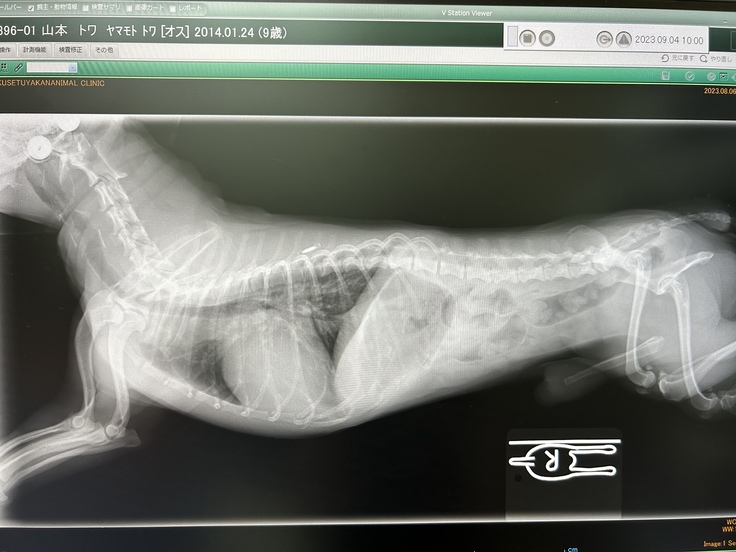

かかりつけの動物病院での掲載の許諾を得ております

手術を行う動物病院での掲載の許諾を得ています

かかりつけの動物病院での掲載の許諾を得ています

動物病院での掲載の許諾を得ています

■4.掲載している資料の掲載許諾について

診断書や診療明細書などの資料は全て動物病

院からの掲載の許諾を得ています。